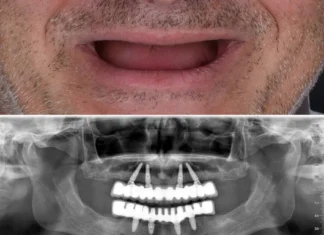

Affordable All-on-4 Dental Implants in Brisbane: Your Comprehensive Guide

Introduction: Are you considering All-on-4 dental implants but worried about the cost? Sandgate Bayside Dental is here to make this transformative procedure accessible to...